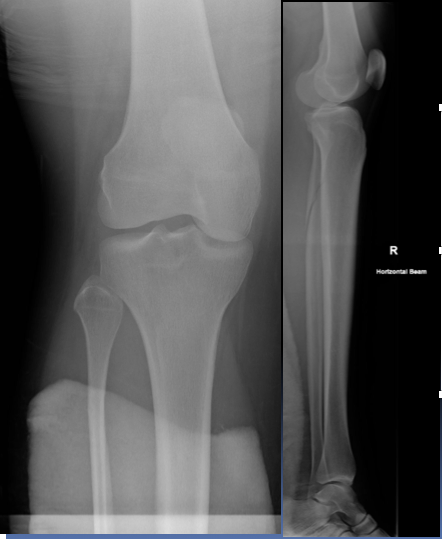

This 75 year old woman presented with difficulty walking and knee pain. How would you describe these X-rays?

A 30 year old man presented to the ED with left knee pain after a cycling accident.

On examination there was no deformity, but it was painful for him to weight-bear. Movements of his knee were painful, and this limited his movements.

What is a lipohemarthrosis?

Results from an intra-articular fracture with escape of fat and blood from the bone marrow into the joint, and is most frequently seen in the knee.